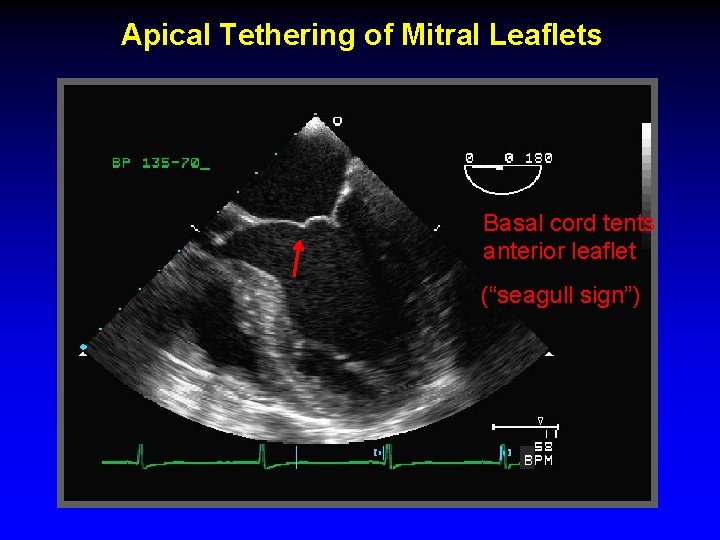

Apical Tethering of Mitral Leaflets Basal cord tents anterior leaflet (“seagull sign”)

Basal cord tents anterior leaflet (“seagull sign”) Increased tenting area